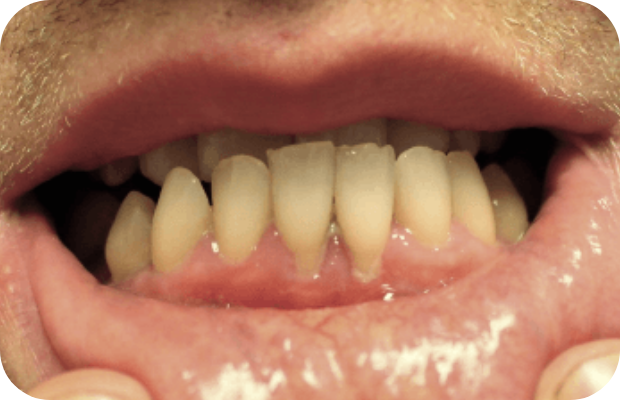

PLGD-1 lesion image gallery

Images of ligneous lesions in real patients with PLGD-1